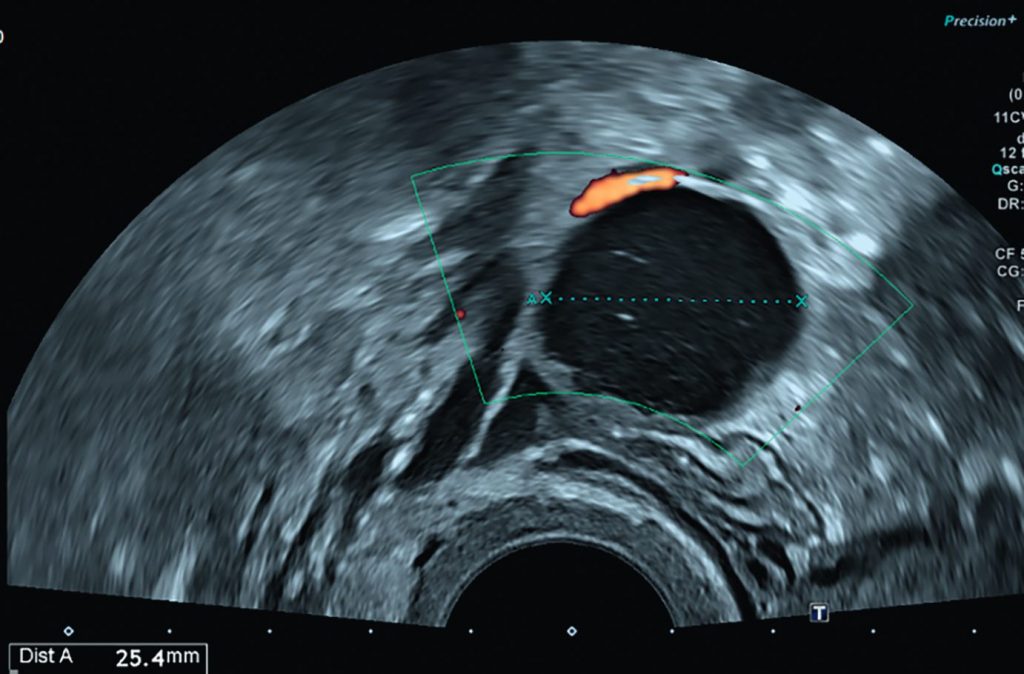

Fig. 20.10 A. Patiente de 45 ans présentant une douleur pelvienne latéralisée à gauche. B. Patiente de 21 ans, nulligeste, découverte fortuite d’une masse ovarienne sur l’échographie réalisée pour contrôle de la pose d’un dispositif utérin.

A. L’échographie endovaginale retrouve une formation kystique uniloculaire pure ovarienne gauche, de parois fines, sans portion tissulaire, ni hypervascularisation au doppler couleur. Le contrôle échographique réalisé à 3 mois ne met plus en évidence la formation kystique, ce qui confirme son caractère fonctionnel. B. L’échographie endovaginale met en évidence une formation hyperéchogène ovarienne gauche avec hypervascularisation au doppler couleur, témoignant d’une volumineuse portion tissulaire, en faveur d’un kyste organique.

Source : CERF, CNEBMN, 2022.